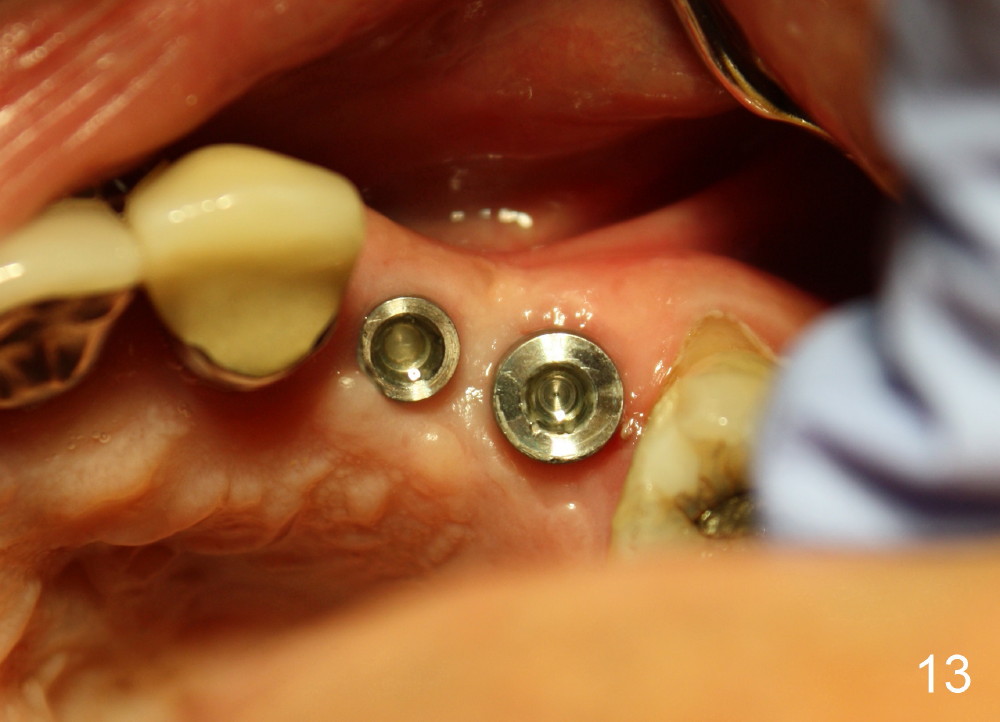

Three month follow-up shows that the gingiva and bone heal around these two implants (Fig.13-15).  Crowns are cemented 4.5 months postop (Fig.16).  There is no or minimal bone loss 9 months post cementation (Fig.17, as compared to Fig.15).  The bone is stable around the implants 18 months post cementation (Fig.18 panoramus).  Root canal therapy is done at #14 between the last follow up appointments.